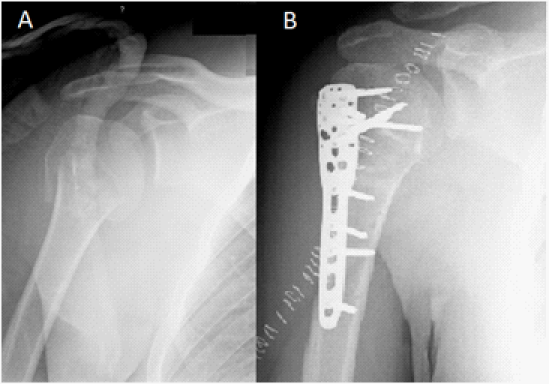

Of the 10 patients, 3 were male and 7 were female. Majority of the patients were elderly or middle aged. The average duration of follow up was 23±3 (range 16-24) weeks. Eight patients had uneventful fracture union at an average of 11.6±0.8 weeks (Table 1). The operated shoulder demonstrated mean forward flexion of 100° and mean abduction of 90°, compared to 168° and 159° respectively in the contra lateral (normal) shoulder. Mean Constant score (Table 2) for the operated shoulder was 62.3 (moderate) as compared to 90.3 for the contra lateral shoulder. Radiographs demonstrated evidence of excellent healing and well positioned implants (Figure 3). None of the patients exhibited radiographic evidence of avascular necrosis at the final follow-up.

Figure 3 Antero-posterior radiograph of the shoulder showing a three-part fracture of the proximal humerus. (A) Postoperative lateral (scapular-Y) radiograph (B) showing fixation of the fracture with the PHILOS plate.